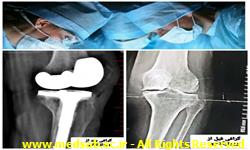

انجام عمل جراحی تعویض مفصل در بیمارستان جوین

رئیس بیمارستان قمربنی هاشم(ع)گفت:عمل جراحی پروتزگذاری (توتال آرتوروپلاستی)دیگری در بیمارستان جوین با موفقیت رقم خورد.

به گزارش وبدا/دکتر زهرا صباغ سجادیه در بیان این مطلب افزود:بیمار خانمی ۷۲ ساله مقیم شهرستان سبزوار که بر اثر کهولت سن و آرتروز شدید زانو رنج می کشید، با تعویض مفصل(پروتز گذاری) زانو در بیمارستان قمربنی هاشم (ع) درمان شد. ️ایشان خاطر نشان نمود: بیمار ابتدا با مراجعه به مراکز درمانی مشهد و عدم تقبّل پرداخت هزینه ی بالا از انجام پروتز گذاری منصرف و سپس با مراجعه به بیمارستان قمربنی هاشم (ع)این عمل جراحی با هزینه ی دولتی، توسط دکتر محمد داود رضایی پزشک متخصص ارتوپد با موفقیت انجام شد. ️ دکتر صباغ در پایان گفت: در بیمارستان قمربنی هاشم(ع) جوین علاوه بر عمل های جراحی ارتوپدی، تعویض مفصل زانو،شانه،هیپ،ران و... زیرنظر پزشکان متخصص ارتوپدی(دکتر محمد داود رضایی-دکتر سیدعلی اصغر سیّدی فرد) انجام میگردد.